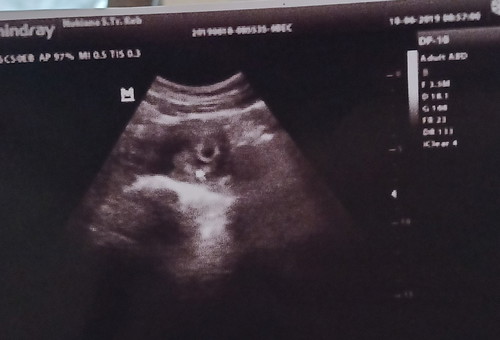

hasil USG perkiraan 6-7 weeks

Permisi, bunda.. Kmrn saya USG dan hasilnya kata Bu bidan masih terlihat kantong kehamilannya saja. Dan katanya normal untuk usia 5-7 minggu. Berhubung saya pernah baca ttg BO, daya jd worry kalo saya jg mengalami ini. Apa betul wajar jika masih usia segutu hanya terlihat kantong kehamilan saja? Trimakasih